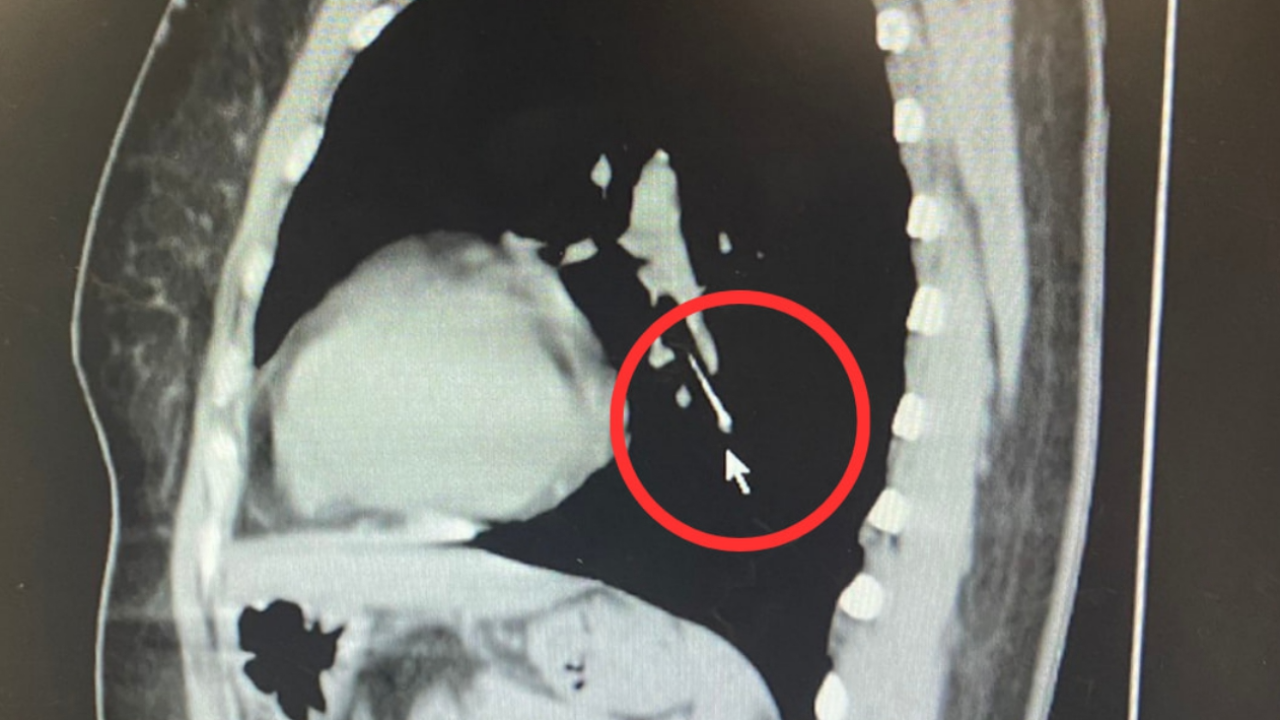

โดยระบุว่า ผู้ป่วยหญิงอายุ 49 ปี ให้ประวัติว่าขณะเย็บผ้า ได้คาบเข็มหมุดไว้ในปาก ต่อมามีอาการสำลักเข็มหมุดหลุดลงคอ จึงได้มาตรวจที่ รพ.นครพิงค์ ทำการตรวจเอกซเรย์คอมพิวเตอร์ พบว่าเข็มหมุดหลุดลงไปคาอยู่ในหลอดลมปอดข้างซ้าย ทีมห้องส่องกล้องระบบทางเดินหายใจ นำโดย นพ.กาจบัณฑิต สุรสิทธิ์ จึงได้ทำการส่องกล้องคีบเข็มหมุดในหลอดลมออกมาได้อย่างปลอดภัย ขณะนี้ผู้ป่วยอาการปลอดภัย แพทย์อนุญาตให้กลับบ้านได้แล้ว